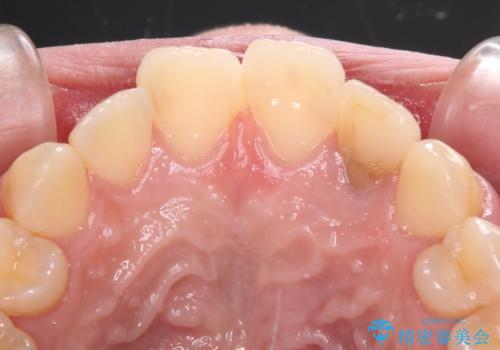

- 根管治療後に10年以上経過し、変色した前歯を気にして来院された患者様です。

根管治療はやり直さずに、ファイバーポストを使用した土台を植立してオールセラミッククラウンにて補綴することとしました。